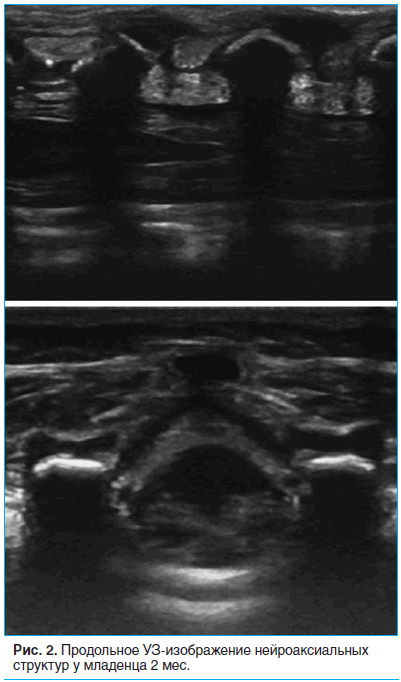

Далее с поворотом датчика на 90° по часовой стрелке мы получали продольное изображение позвоночника (рис. 2). Заметны полукруглые поперечные отростки поясничных позвонков с подлежащей акустической тенью, а также межпозвонковые промежутки между ними. В первом межпозвонковом промежутке отмечается яркая, гиперэхогенная линия желтой связки с подлежащим эпидуральным пространством и твердой мозговой оболочкой, укрывающей конус спинного мозга.

При этом соседние остистые отростки были видны как яркие, слегка наклоненные каудально, гиперэхогенные образования с выраженной акустической тенью. В межпозвонковом пространстве между ними распространению УЗ-луча ничто не мешает, поэтому оно выглядит как изоэхогенная серая полоса между темными анэхогенными тенями от остистых отростков. Смещая датчик выше или ниже, мы выбирали наиболее широкий межпозвонковый промежуток (L4–L5 или L3–L4) у каждого больного. На выбранном промежутке мы делали отметку в середине длинной оси датчика, получая вторую точку, от которой строился перпендикуляр к линии, соединяющей соседние остистые отростки на этом уровне. Таким образом мы получали наилучшую точку для проведения иглы при выполнении люмбальной пункции.